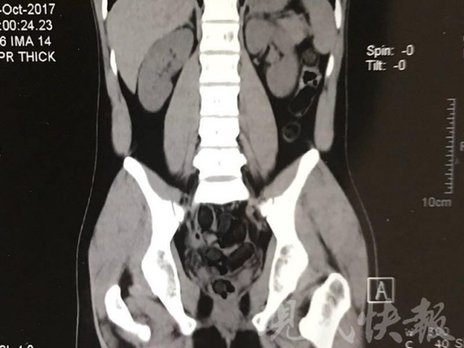

小伙體內(nèi)藏毒300余克 CT掃描圖密密麻麻

小伙體內(nèi)藏毒300余克 CT掃描圖密密麻麻全是蠶蛹

由于毒品在體內(nèi)一旦泄露有可能致命,警方第一時間將阿永帶到醫(yī)院進行檢查。CT 掃描的結(jié)果顯示,阿永體內(nèi)布滿了密密麻麻的白色圓柱狀固體,就像一粒粒的蠶蛹。在南京市公安局鼓樓分局二板橋派出所,阿永分四次排出了毒品,毛重369.99克。經(jīng)訊問,阿永交代了自己全部的犯罪事實。目前,阿永已被刑事拘留。